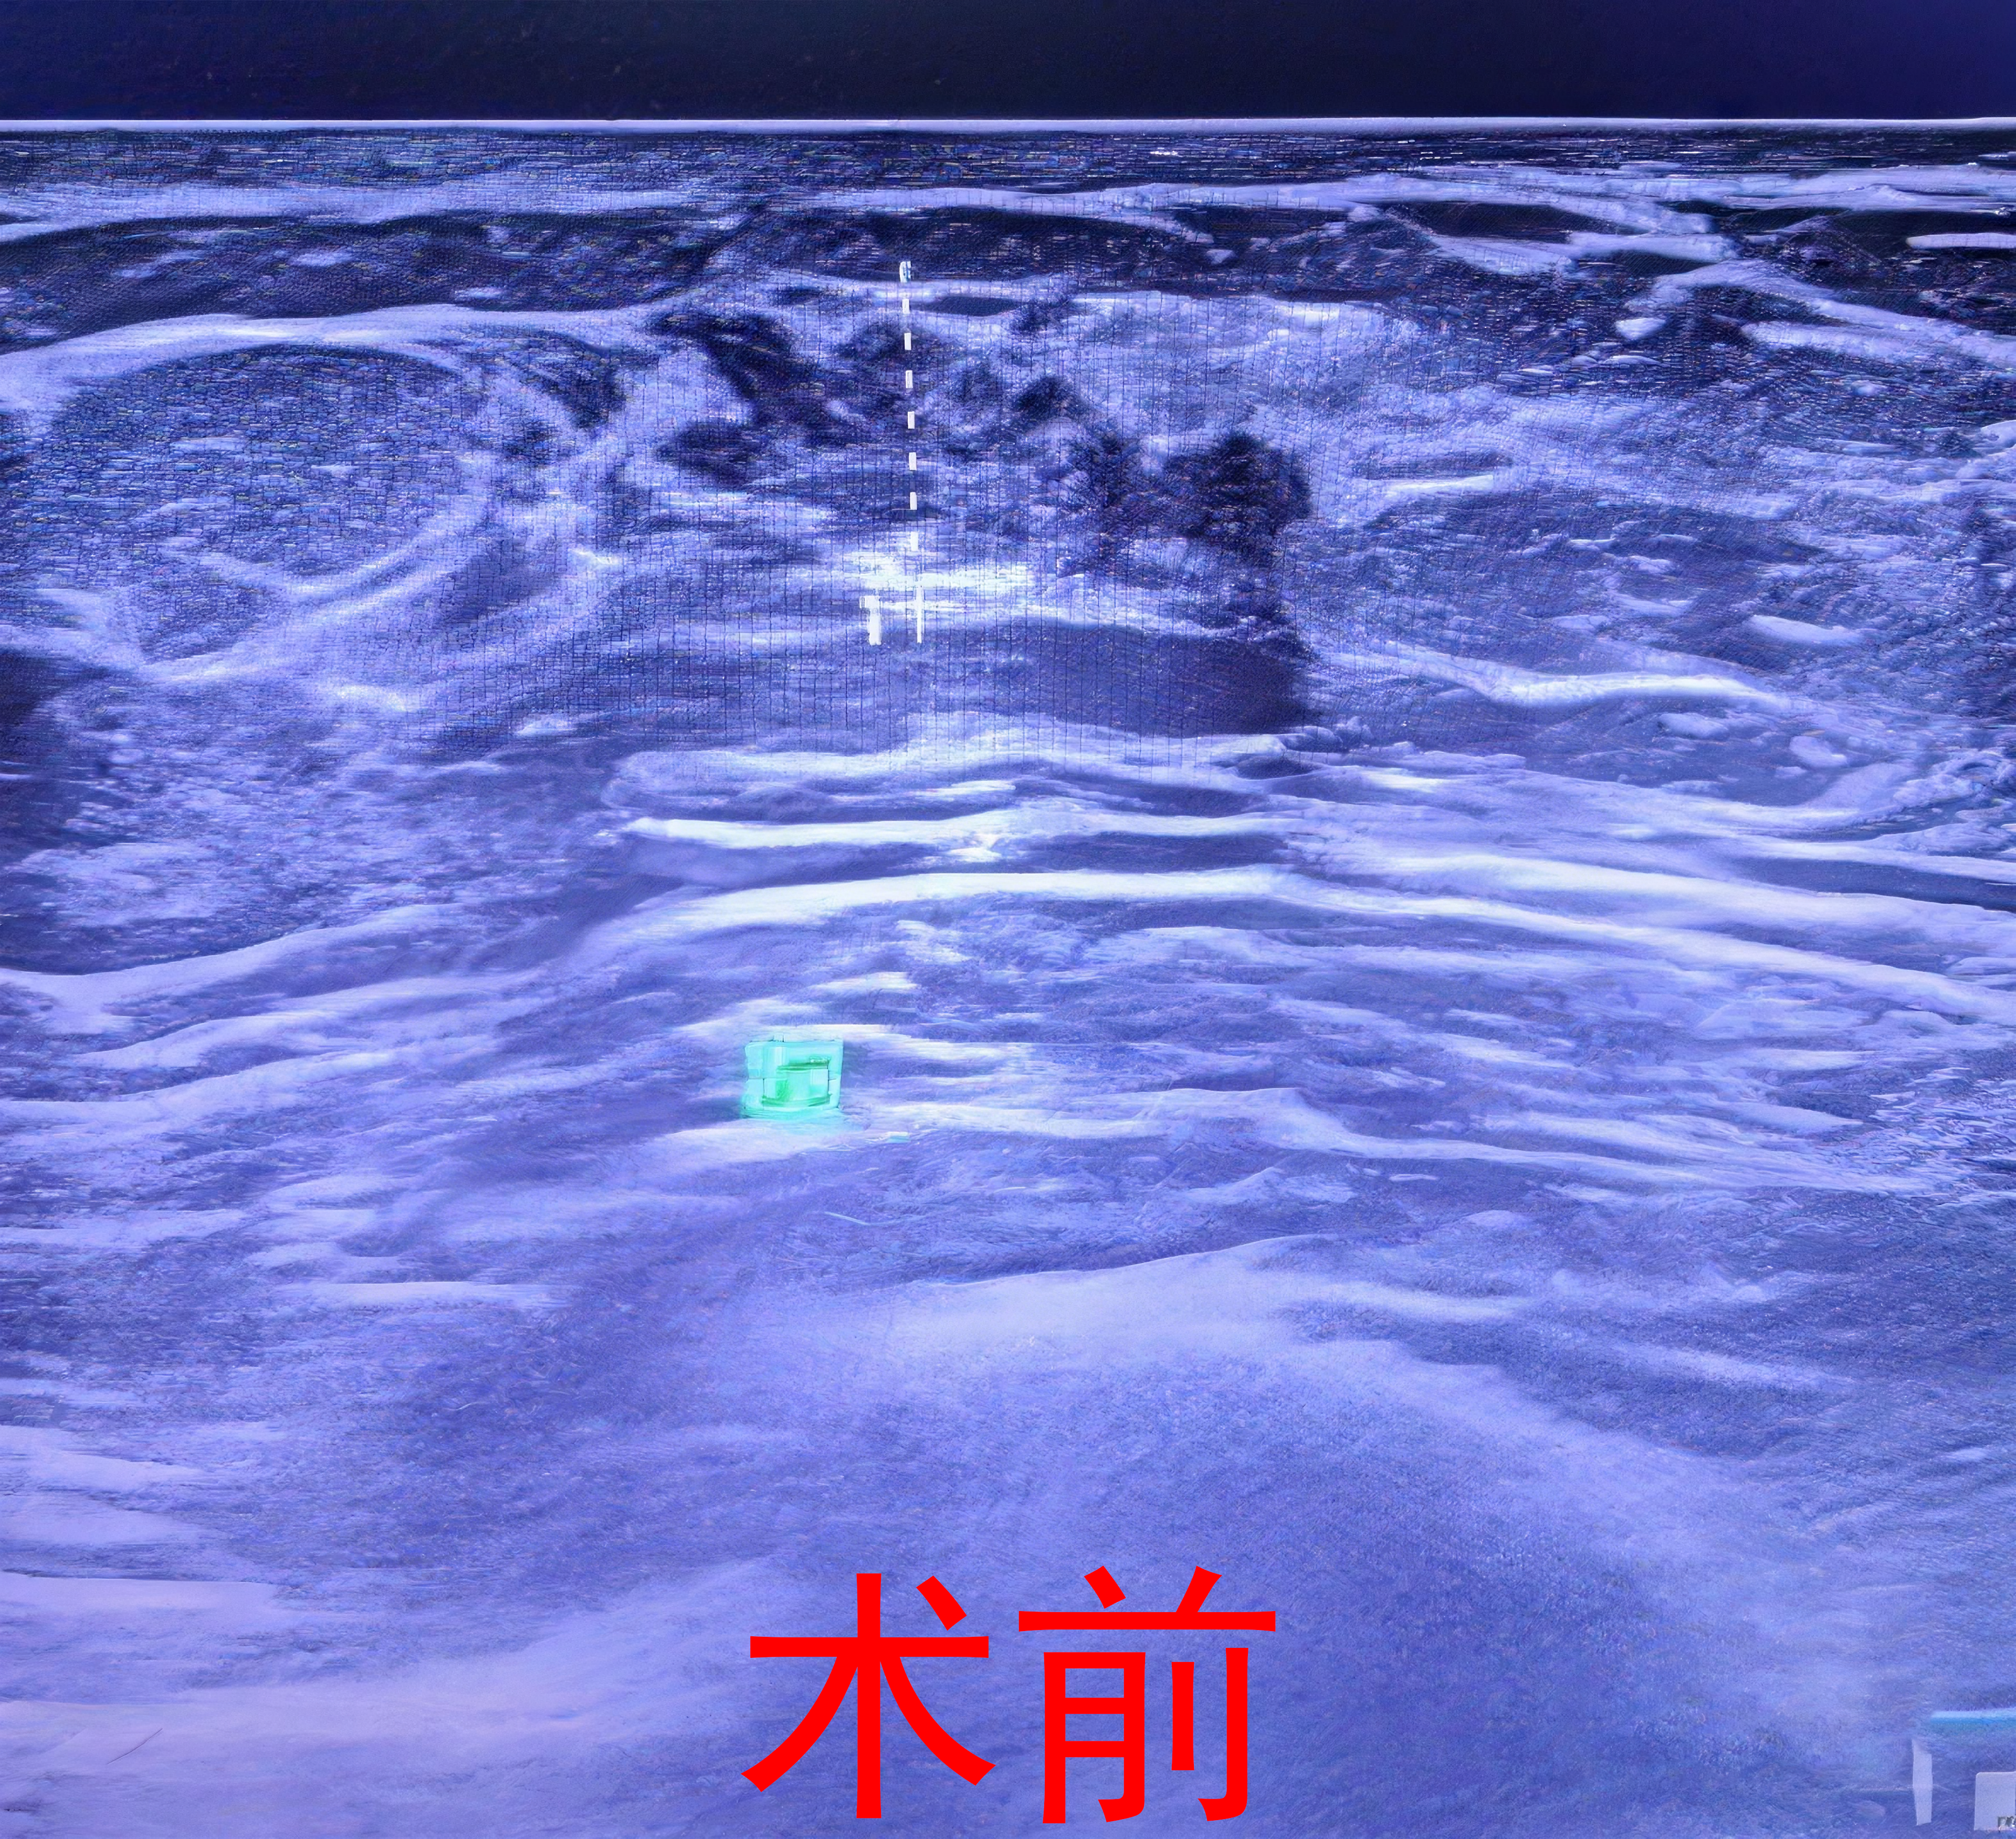

接诊后,我院乳腺外科团队详细询问患者病史,进行全面体格检查,并结合乳腺超声、性激素六项等辅助检查,综合评估后明确诊断为双侧男性乳房发育症。针对患者的年龄、病情特点及对外观的需求,科室团队经充分评估与沟通,为其制定了个性化微创治疗方案——腔镜下双乳皮下腺体切除术。

该术式是治疗男性乳房发育的常用微创方案,其特点在于切口小且位置隐蔽(多选择腋下等隐蔽部位)、创伤小、术中出血少、术后恢复快、外观满意度高。该技术可在腔镜辅助下精准切除异常发育的乳腺腺体,同时最大程度保留乳房正常组织与外观形态,契合年轻患者的诊疗需求。

手术由科室经验丰富的医师团队主刀,在麻醉科、手术室的密切配合下,顺利完成双乳皮下腺体切除操作,手术过程平稳,术中出血量少。术后,患者在医护团队的精心护理下,切口愈合良好,乳房疼痛、触压痛症状完全消失,双乳外观恢复正常,患者及家属对治疗效果表示满意,现已顺利出院回归正常生活。